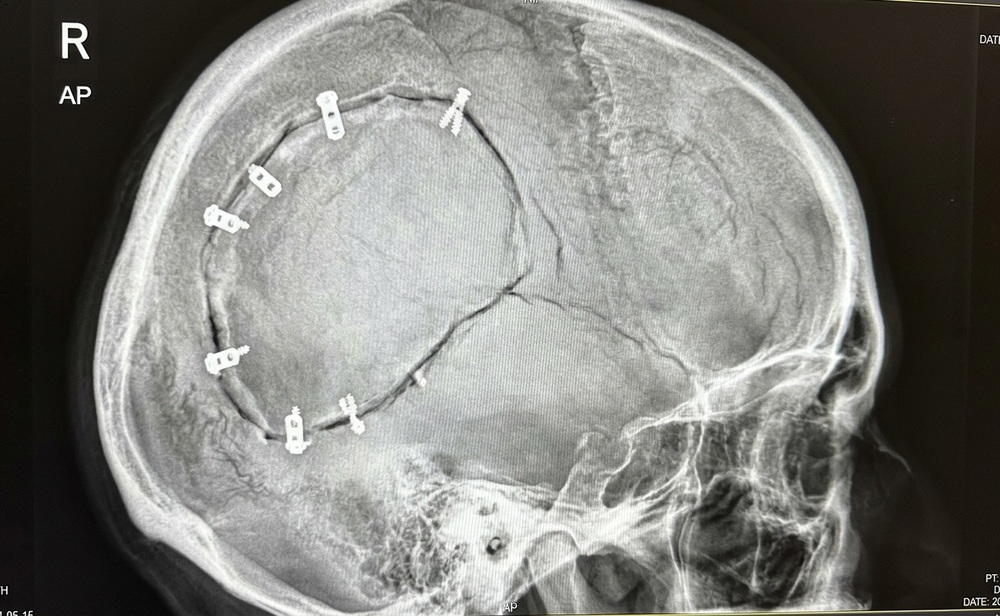

В Саратовской области врачи спасли 16-летнего подростка, которому потребовалась экстренная трепанация черепа после падения с велосипеда.

О деталях сложной операции сообщили в пресс-службе СОДКБ. Юноша поступил в больницу в тяжёлом состоянии с ушибом головного мозга и переломом основания черепа. Жизнеугрожающая ситуация возникла из-за удара головой о камень, в результате чего образовалась обширная гематома. Дежурный нейрохирург незамедлительно провёл вскрытие черепной коробки для удаления скопившейся крови.

Сложное хирургическое вмешательство прошло успешно, а послеоперационный период протекает без осложнений. Сейчас пациента уже перевели из реанимации в обычную палату. Подросток стабильно идёт на поправку под наблюдением специалистов.